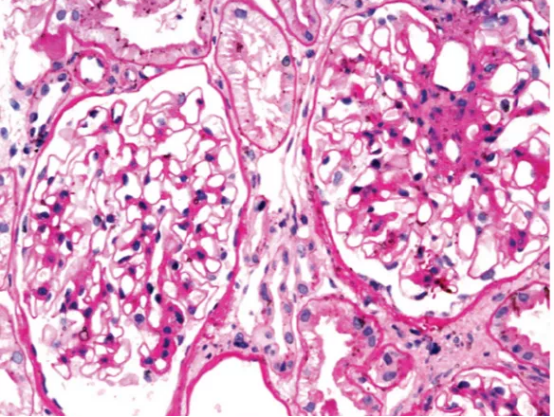

PAS染色显示基底膜、系膜基质、糖原及糖蛋白呈紫红色,细胞核呈蓝色,非常适合于观察基底膜病变、细胞外基质的增多、各种细胞的增生及渗出、鉴别沉积的物质是否富含糖链等病变。

图 1:膜性肾病中的PAS染色,细胞核呈蓝色,基底膜及肾小球系膜基质呈红色。